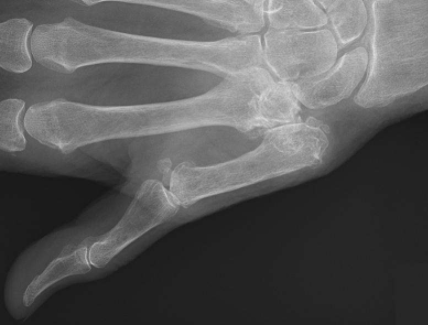

因为手指活动不灵活,影响到正常的生活,所以挂了个三甲医院的骨科专家门诊,医生先是给我开单做了个CT检查,看了CT结果告知确诊为腱鞘炎。

手指发病就是人体手指长期劳作,肌肉过度活动使得肌腱长期过度摩擦,即可发生肌腱和腱鞘的损伤性炎症,引起肿胀,会出现类似黄豆粒大小结节的关节疼痛,手指屈伸活动不灵活,并伴有弹响现象。